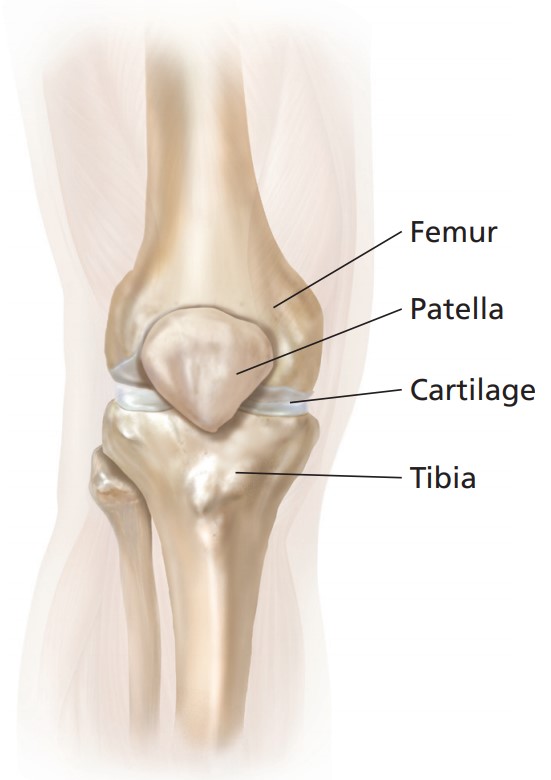

การผ่าตัดเปลี่ยนข้อเข่าเทียมบางส่วน หรือเรียกสั้นๆ ได้ว่า UKA คือ การผ่าตัดเอาผิวข้อเข่าเฉพาะส่วนที่เสียหายหรือเสื่อมสภาพออก นั่นคือด้านในหรือด้านนอก (Medial or Lateral Compartment) เพียงด้านเดียว ผิวข้อเข่าที่เสื่อมจะถูกแทนที่ด้วยโลหะอัลลอยด์ โดยมีแผ่นโพลีเอทิลีนซึ่งทำหน้าที่เป็นตัวรองรับแทนที่หมอนรองกระดูกเดิมกั้นระหว่างโลหะ

(Figure 5-8) วิธีนี้ถือเป็นนวัตกรรมพิเศษที่คิดค้นขึ้นเพื่อรักษาพยาธิสภาพที่เข่าเฉพาะกลุ่มผู้ป่วยให้ตรงจุดมากที่สุด และเป็นเทคโนโลยีการผ่าตัดแผลเล็ก ที่ช่วยเก็บผิวข้อเข่ารวมถึงเอ็นและเนื้อเยื่อเดิมที่ยังมีสภาพดีไว้ ทำให้เกิดความรู้สึก เสมือนธรรมชาติ หลังการผ่าตัด ซึ่งเป็นจุดเด่นสำคัญของการผ่าตัดด้วยวิธีนี้

(Figure 5-8: Unicompartmental Knee Arthroplasty: UKA)

โดยทั่วไปแล้วข้อเข่าเสื่อมที่เกิดจากการใช้งานตามวัย มากกว่า 90 % มักจะเริ่มมีการเสื่อมที่ผิวข้อเข่าด้านในเพียงด้านเดียว ทำให้เหมาะต่อการรักษาโดยการผ่าตัดเปลี่ยนข้อเข่าบางส่วน ซึ่งเป็นวิธีที่สามารถเก็บรักษาผิวข้อเข่าหรือกระดูกอ่อน ตลอดจนเส้นเอ็นต่างๆ ภายในข้อเข่าที่ยังมีสภาพดีไว้ แทนที่จะทำการผ่าตัดเปลี่ยนข้อเข่าทั้งหมด และยังให้ความรู้สึกเสมือนธรรมชาติของข้อเข่าได้อีกด้วย